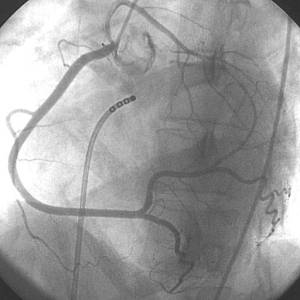

Διαγνωστικός καθετηριασμός (επιβεβαίωση της διάγνωσης)